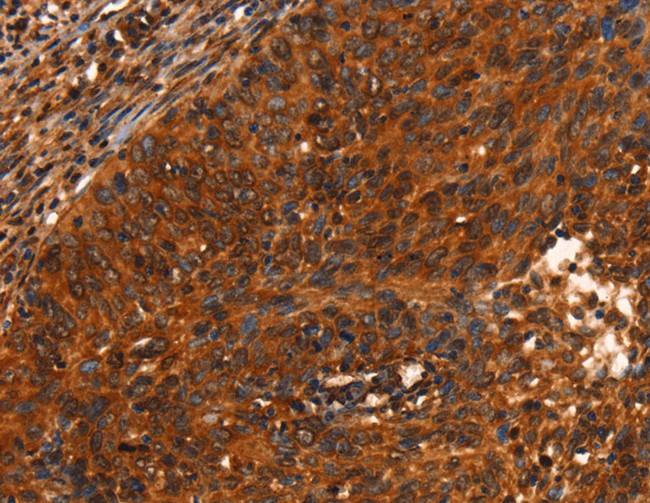

IHC (Immunohiostchemistry)

(Immunohistochemistry of paraffin-embedded Human cervical cancer using PRKD1 Polyclonal Antibody at dilution of 1:40)